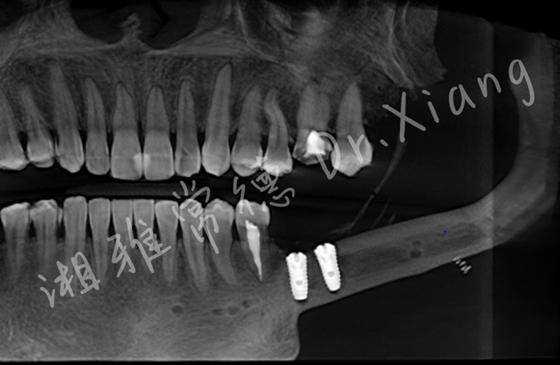

近日,湘雅常德医院口腔科成功实施首例腓骨移植区种植牙手术,标志着我院在口腔颌面外科与种植修复领域取得重大突破。该手术通过多学科协作与数字化精准医疗技术,为一例成釉细...